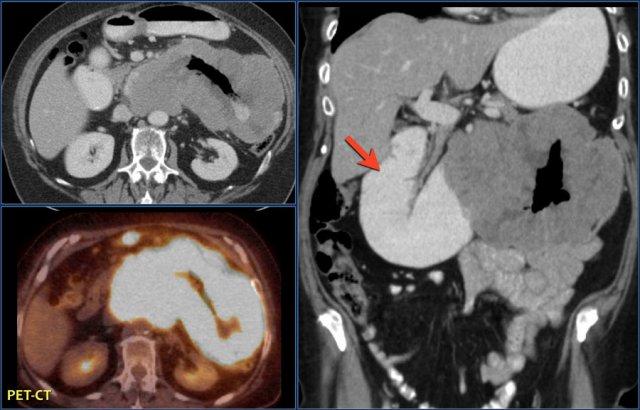

GIST ác tính chủ yếu phát triển ngoài lòng ruột và có thể biểu hiện hoại tử, xuất huyết, vôi hóa (sau điều trị) và hình thành đường rò.

Điển hình, GIST là một khối giới hạn rõ, phát triển ngoài lòng ruột (exophytic), ngấm thuốc không đồng nhất và có ranh giới rõ ràng với mạc treo ruột.

Khối phát triển trong lòng ruột ít gặp hơn nhiều.

Tắc ruột hiếm gặp vì GIST không xâm lấn toàn bộ chu vi thành ruột, khác với ung thư biểu mô tuyến (adenocarcinoma).

Khác với u carcinoid, tổn thương nguyên phát trong GIST thường có kích thước lớn.

Cả GIST và u lympho đều có thể gây giãn phình dạng túi (aneurysmal dilation) của lòng ruột.

Di căn gan thường tăng sinh mạch (hypervascular) và có thể bị bỏ sót nếu chỉ chụp CT đơn thì tĩnh mạch cửa.

Di căn hạch bạch huyết thường không gặp.

Nếu phát hiện hạch to, cần cân nhắc chẩn đoán khác.

Di căn mạc treo hoặc mạc nối lớn gặp nhiều hơn trong bệnh tái phát so với lần phát hiện đầu tiên.

Điều này được cho là do rò rỉ khối u trong quá trình phẫu thuật.

Các tổn thương di căn này có thể dễ bị bỏ sót do thường có trung tâm giảm tỷ trọng.

Sau hóa trị (Imatinib hoặc Gleevec), các tổn thương di căn gan và mạc treo trở nên giảm sinh mạch hoặc thậm chí dạng nang.

Mặc dù đã phẫu thuật cắt bỏ triệt căn, 40-90% bệnh nhân có tái phát bệnh tại gan hoặc mạc treo.

Gleevec có thể được chỉ định trong trường hợp bệnh di căn.

Tái phát bệnh sau phẫu thuật cắt bỏ GIST với hình ảnh các tổn thương di căn gan giảm tỷ trọng và một khối di căn phúc mạc lớn không đồng nhất.